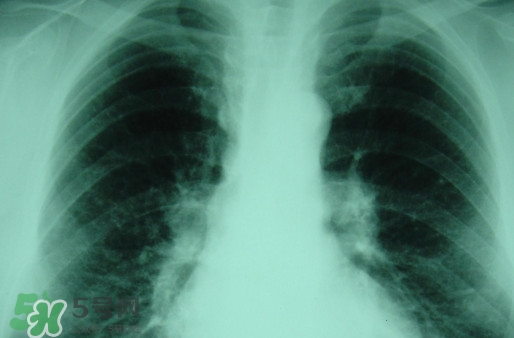

塵肺病能治愈嗎?塵肺病能活多久

對(duì)于塵肺病,很多人都是陌生而又熟悉,因?yàn)槠渚褪且环N人體肺部滿身灰塵的病癥,一般從事煤礦或是珠寶打磨行業(yè)人群患病率高。那么,塵肺病能治愈嗎?塵肺病能活多久?